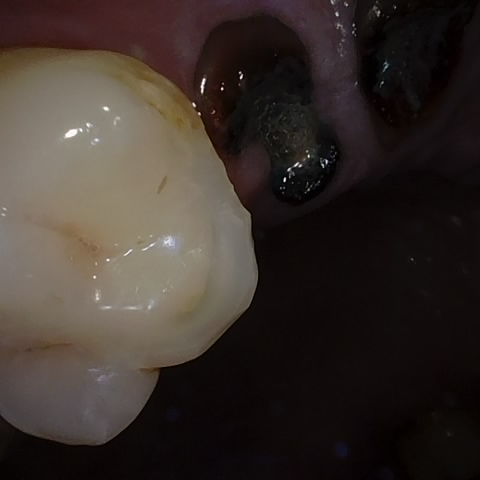

Annotated as "Good"